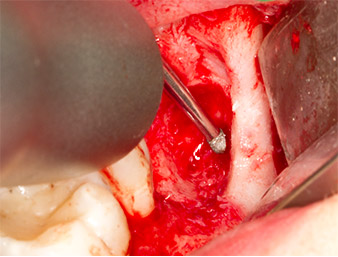

Tessuto di granulazione

Fig. 4: Due retrattori Langenbeck e una curette espongono l'area dell'intervento. È visibile il tessuto di granulazione della prima osteotomia non completamente cicatrizzata.